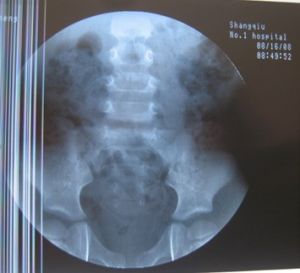

先天性脊柱裂先天性脊柱裂是一種先天性的脊柱裂隙,可發生於脊柱前方的椎體,或脊柱後方的椎弓,而以後方裂為多見。當胚胎時期發育發生障礙以致脊椎椎弓未能閉合時,可形成脊柱裂。一般多發生於腰骶椎。通過此裂隙,脊髓管的內容物可膨出,脊髓膜也常發育不良。造成這種畸形的病因尚不明確。有人認為,這與妊娠早期胚胎受到化學性或物理性的損傷有關,也有人認為孕婦經過x線照射可發生胎兒畸形。

先天性脊柱裂形成於母親孕早期,約在孕40天左右,由於多種因素造成神經軸及中胚層發育缺陷,導致神經管和椎管閉合不全。

先天性脊柱裂分為顯性脊柱裂和隱性脊柱裂兩大類: